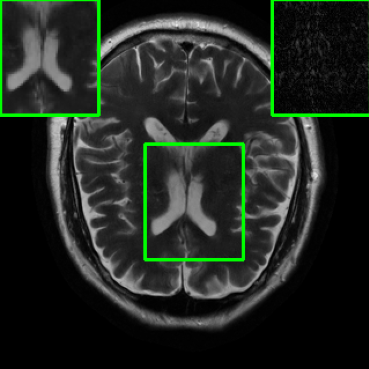

| Ground Truth | Initial | Global | LONDN-MRI | LONDN-MRI | Oracle |

| (1 iteration) | (2 iterations) | ||||

![]() |

| PSNR = dB | PSNR = 19.41 dB | PSNR = 26.52 dB | PSNR = 27.76 dB | PSNR = 27.85 dB | PSNR = 27.92 dB |

Performance on the Stanford FSE Dataset: We also performed image reconstructions with the Stanford multi-coil FSE dataset, which is a smaller dataset. We used same settings for the networks and training as in Section IV-A. Table III shows that LONDN-MRI significantly outperforms the globally learned MoDL network at both 4x and 8x acceleration. This indicates benefits for the proposed framework for smaller, more diverse datasets. Figs. 7 and 8 display visual comparisons that show the LONDN-MRI scheme recovering sharper features than the globally learned network.

| Acceleration | Global | LONDN-MRI | LONDN-MRI | Oracle |

|---|---|---|---|---|

| (1 iteration) | (2 iterations) | |||

| 29.45 | 31.49 | 31.56 | 31.67 | |

| 27.25 | 29.35 | 29.43 | 29.60 |